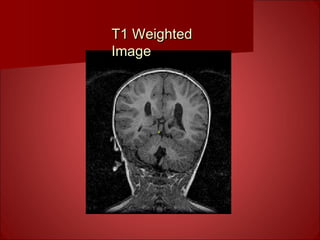

T1 Contrast

• Technique: use intermediate timing

between RF shots (intermediate TR) and

very short TE, also use large flip angles for

GRE & MEMP

• Useful for creating gray/white matter

contrast for anatomical reference

• ~1 mm resolution

T1 WeightedT1 Weighted

ImageImage